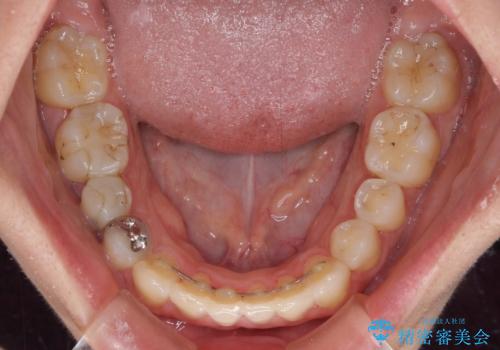

上下の骨幅を改善したことで、スムーズに歯列矯正を行うことができました。

奥歯の咬み合わせを改善する必要があったため、治療は長期化しましたが、きっちりと仕上げることができました。